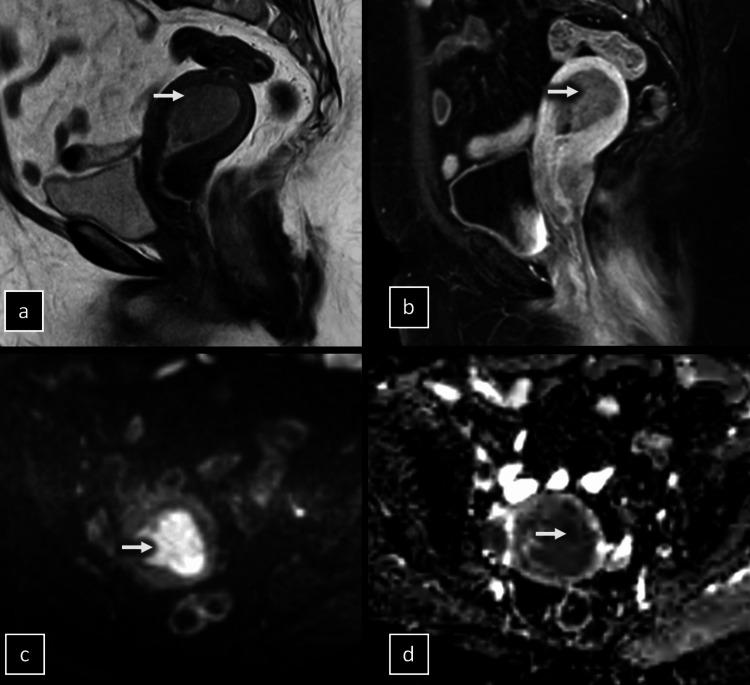

Endometrial cancer (EC) is the most common gynecological malignancy. Accurate preoperative staging is essential for guiding treatment. The depth of myometrial invasion is a key prognostic factor. This prospective study aimed to evaluate the added benefit of diffusion-weighted imaging (DWI) compared to T2-weighted imaging (T2WI) and dynamic contrast-enhanced MRI (DCE-MRI) for the preoperative assessment of myometrial invasion in EC.

Thirty-one patients with histologically confirmed EC underwent preoperative pelvic MRI on a 1.5T scanner. T2WI, DWI (b-values 0, 1000 s/mm), and DCE-MRI were performed. Two radiologists independently assessed myometrial invasion on T2WI, T2WI + DWI, and T2WI + DCE-MRI. Histopathology after hysterectomy was the reference standard. Diagnostic accuracy, sensitivity, specificity, positive predictive value (PPV), and negative predictive value (NPV) were calculated for each MRI protocol, with separate analyses for superficial (<50%) and deep (≥50%) myometrial invasions.

The accuracy for assessing superficial invasion was 61.3% for T2WI, 87.1% for T2WI + DWI, and 87.1% for T2WI + DCE-MRI. For deep invasion, accuracy was 64.5% for T2WI, 90.3% for T2WI + DWI, and 90.3% for T2WI + DCE-MRI. Sensitivity, specificity, PPV, and NPV for T2WI + DWI and T2WI + DCE-MRI were high and comparable (88.9-91.7%) for both superficial and deep invasions. T2WI had markedly lower sensitivity and specificity. The differences between T2WI and the functional MRI protocols were statistically significant (p < 0.01).

DWI and DCE-MRI significantly improve the diagnostic performance of MRI for the preoperative assessment of myometrial invasion depth in EC compared to T2WI alone. DWI + T2WI and DCE-MRI + T2WI demonstrate comparable high accuracy. DWI may be preferable since it is faster and avoids contrast administration.